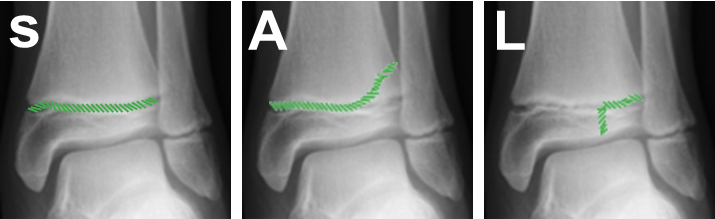

Growth plate injuries

In children, the weakest point around a joint is the growth plate. In adults, it is usually the ligaments of the joint. Growth plate fractures occur in typical patterns and are described using the Salter-Harris classification. The word SALTER (I – Straight across, II – Above, III – Lower, IV – Trough Everything and V – cRush) is a useful acronym to remember this classification.

- Type II fractures are by far the most common

- Type III and IV are intra-articular fractures and require anatomical reduction.

- Type V is associated with a high rate of growth disturbance.